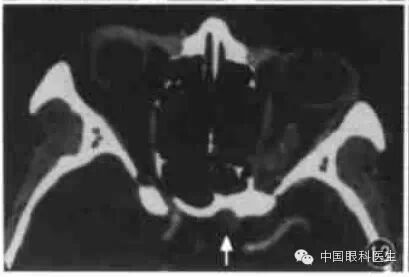

3.眼上静脉增粗

现代高分辨力CT可显示正常眼上静脉。眼上静脉起自内眦部,于视神经上方与上直肌间穿过眶中部,达眶上裂。临床上常见的眼上静脉增粗主要是颈动脉-海绵窦瘘。水平CT扫描显示视神经上方层面条索状高密度影,并自内侧斜向外侧(图14);冠状CT示视神经上方(或内上,外上)圆形高密度影。轻度增粗时需要与对侧比较。

图14 劲动脉海绵窦瘘CT显示右眼上静脉增粗,左侧为正常眼上静脉(箭头)